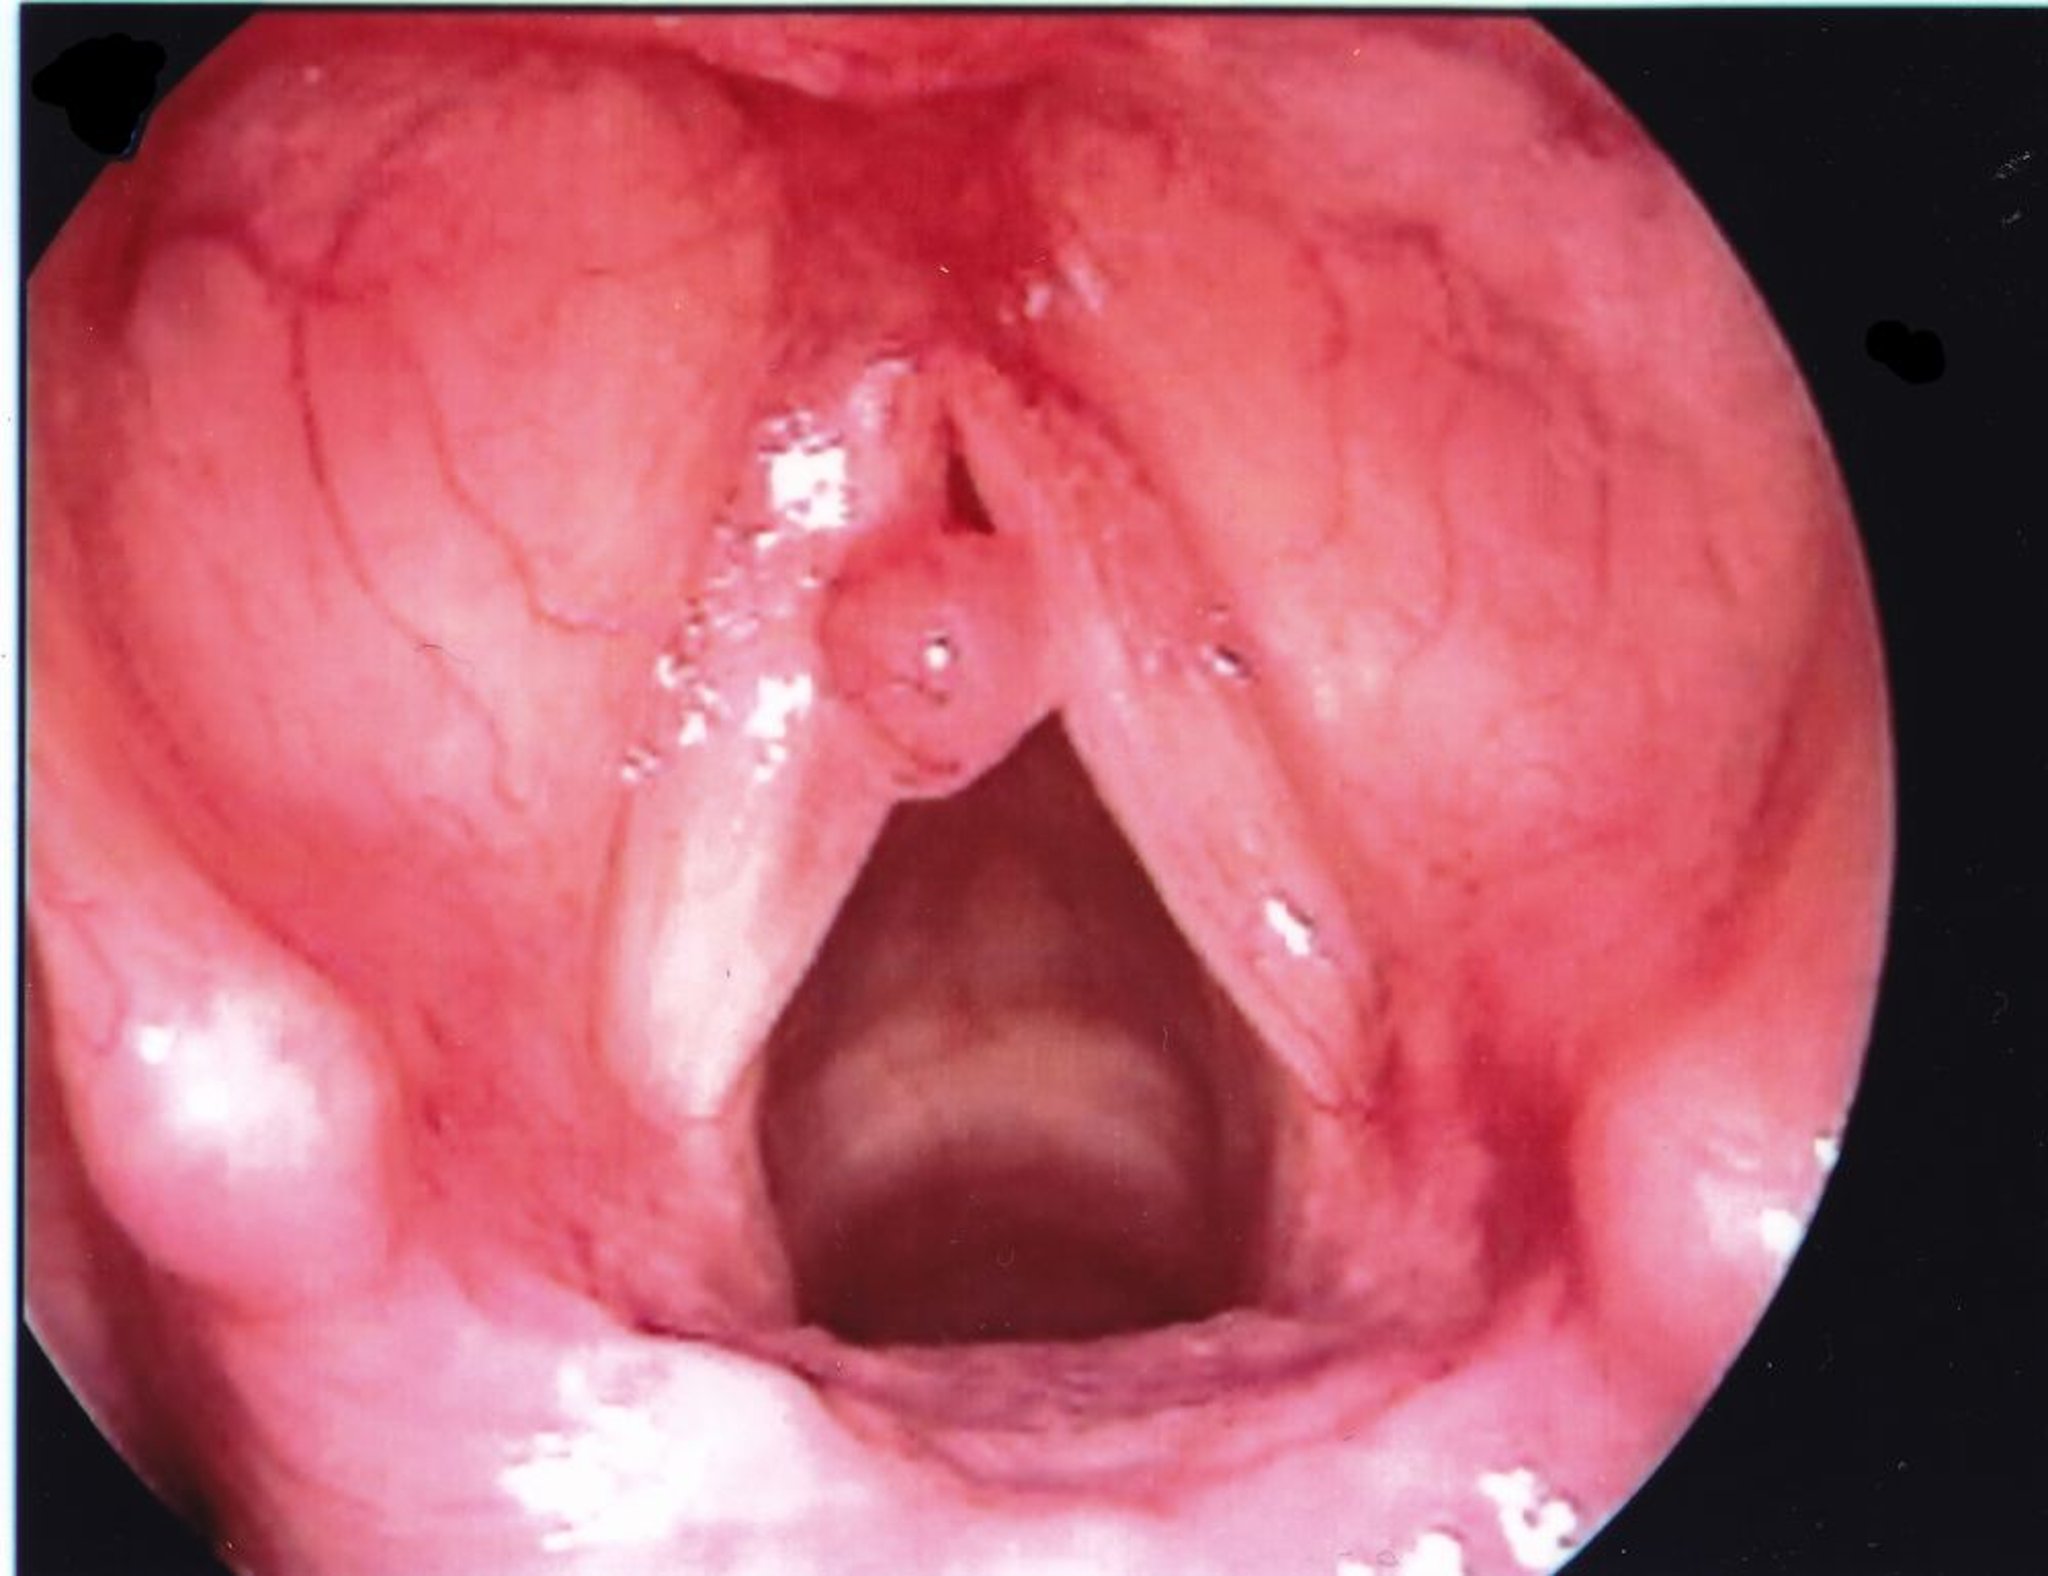

声帯ポリープ

通常,声帯ポリープは片側性にみられ,声帯結節よりも大きい。

Image provided by Eiji Yanagisawa, MD.